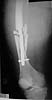

Rt femur

Attached here few x-rays of a multi-trauma patient. He is a 51years old man,sustain MVA at 08/15/99 and refer to our hospital few days ago, more than twoweeks after injury. He sustain Bilateral femoral fracture including femoralneck, A right humerus fracture, right distal radius fx, left open ulnar fx,right tibial plateau (type III) fx and Chopart fracture dislocation of the rightfoot. At the other hospital where he was admitted, He underwent laparotomy andfixation of both femur by reconstruction IMN, application of Ex Fix to thehumerus, and reduction and K.W. fixation of the Rt foot. He is currently stable and conscious. He is scheduled next week for replacing of the Rt IMN to aretrograde nail and pinning (6.5 mm screws) of the neck fracture, fixation ofthe ulna, distal radius and tibial plateau.